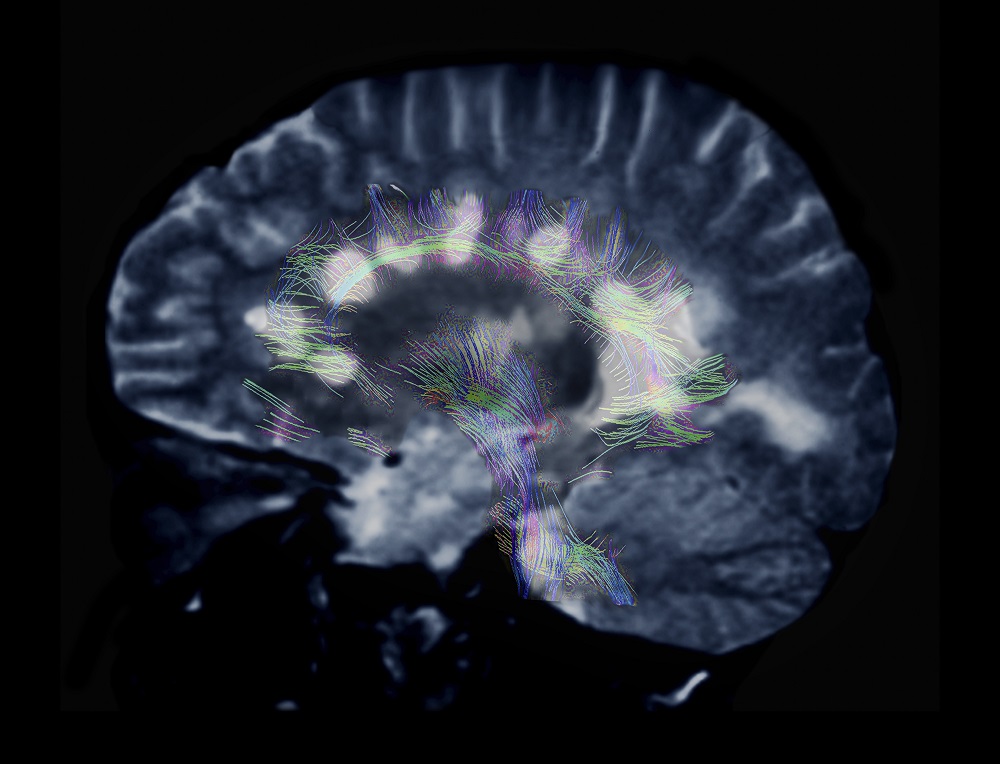

MRI of MS

With the proliferation of more effective therapies, clinicians have expressed concern that traditional, individual outcome measures of treatment response, including annualized relapse rate, lesions shown on magnetic resonance imaging (MRI), and disability progression, may be inadequate to assess overall treatment response. “Composite outcome measures of treatment response that incorporate both clinical and radiologic metrics of disease activity and progression and are potentially more sensitive to the effects of DMTs are now being incorporated into MS clinical trials…,” wrote the authors of a review published in February 2018.2

“NEDA-3 emphasizes the role of inflammatory pathology, reflecting the classical view of MS as a focal disease of the white matter,” according to the recent review. “However, there is growing evidence of diffuse pathology involving both grey and white matter, driven by both inflammatory demyelination and neurodegeneration, that ultimately culminates in brain volume loss.” As such, annualized whole brain volume loss ≤0.4% has been added as a fourth variable.10 The 4-parameter measure is called NEDA-4.

Dr Bermel: The idea of having a defined treatment target in MS gives healthcare providers and patients a monitoring plan and an appropriate expectation for how to tell whether the medication is working. Especially early in a person’s course with MS, disease activity can be occurring without any corresponding symptoms. Having MRI as part of the NEDA target really emphasizes the importance of checking MRI to monitor for subclinical disease activity and changing therapy if there are new or active MS lesions.